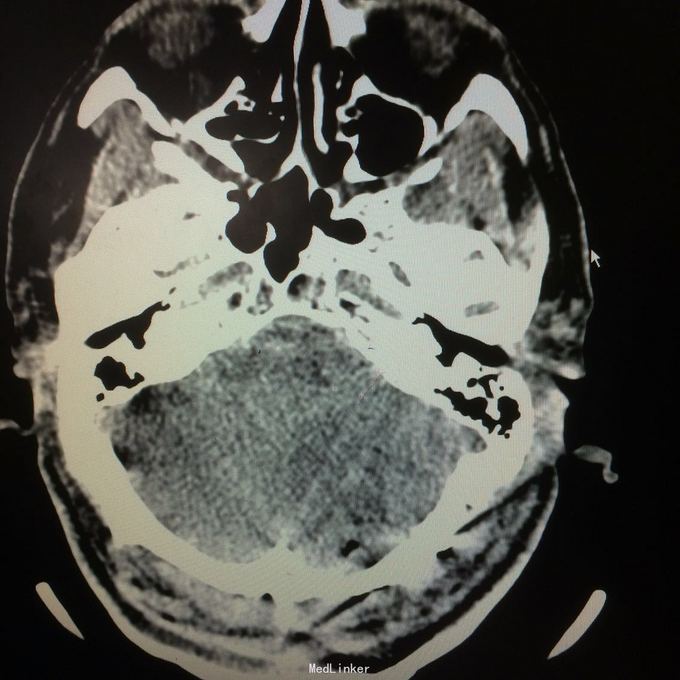

主诉:头晕头痛2年 病史:2年前无明显诱因出现头痛,呈刺痛,程度较重,伴头晕、天旋地转感,1年前查头颅MR提示:左侧小脑半数囊性病变,考虑血管母细胞瘤

查体:神志清楚,病理证阴性 辅助检查:头颅MR提示左侧小脑半数后部囊状占位灶,考虑良性病变。

诊断:左侧小脑血管母细胞瘤 处理:行左侧小脑占位病变切除术,术后病理提示:符合血管母细胞瘤。